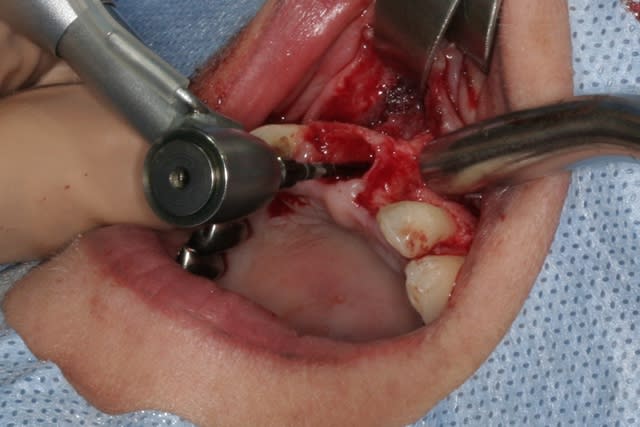

tien, ce matin, extraction de 24/25, curetage méticuleux, forage, comblement du gap, pose des 2 implants qui se sont bloqués à 50Ncm au CA sur les 3 ou 4 mm apicaux, pose des vis de cicat, sutures...35min....tranquille...

Voilà ce que l'on arrive à faire mais ce fut limite!

--

"La seule chose promise d'avance à l'échec, c'est celle que l'on ne tente pas" Paul Emile VICTOR

Interactive dx8dv8 - Eugenol